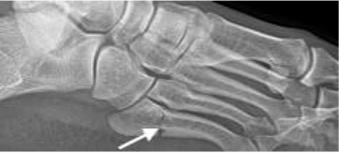

Jones fracture

- Extra-articular transverse fracture at the metadiaphyseal junction of the fifth metatarsal

- Higher chance of non-union due to watershed vascularity